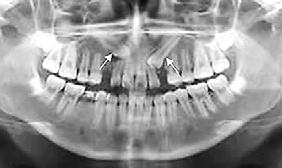

El seguimiento del trayecto canino con un estudio radiográfico postero anterior, lateral de cráneo y ortopantomográfico, a partir de la edad señalada anteriormente, también es una herramienta efectiva que permite obtener un diagnóstico inicial, donde podrá observarse si se ha iniciado la reabsorción radicular del canino deciduo e identificar qué

dirección o trayecto está tomando el canino permanente (Figura 18).

Ubicación del canino

Un método sencillo para obtener el diagnóstico de inclusión canina en proceso o declarada, cuando no se realizó un seguimiento desde una edad temprana, será utilizando como herramienta de diagnóstico inicial, una ortopantomografia, donde al trazar puntos, planos y líneas de referencia en estructuras dentocraneales y en el eje longitudinal del canino propiamente, podremos ubicar tridimensionalmente el sitio de inclusión en proceso de formación radicular (estadio del 6 al 9), o definitivo, cuando el ápice se ha cerrado (estadio 10 de Nolla) y el diente no erupcionó8 (Figura 20).